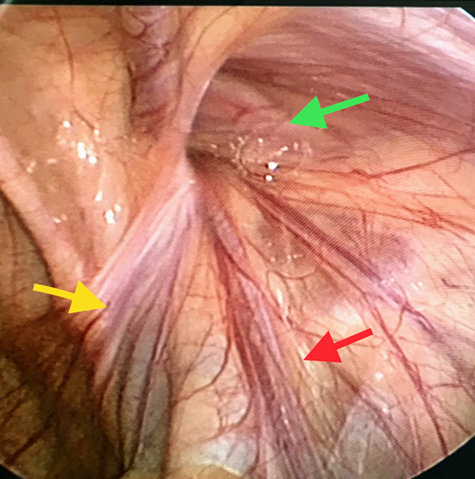

1. Đặt trocart nhỏ ở rốn, quan sát bằng ống soi <5mm. (Ảnh 2)

Ảnh 2: Quan sát qua nội soi: lỗ bẹn sâu (mũi tên xanh lục), bó mạch sinh dục (mũi tên đỏ), ống dẫn tinh (mũi tên vàng)